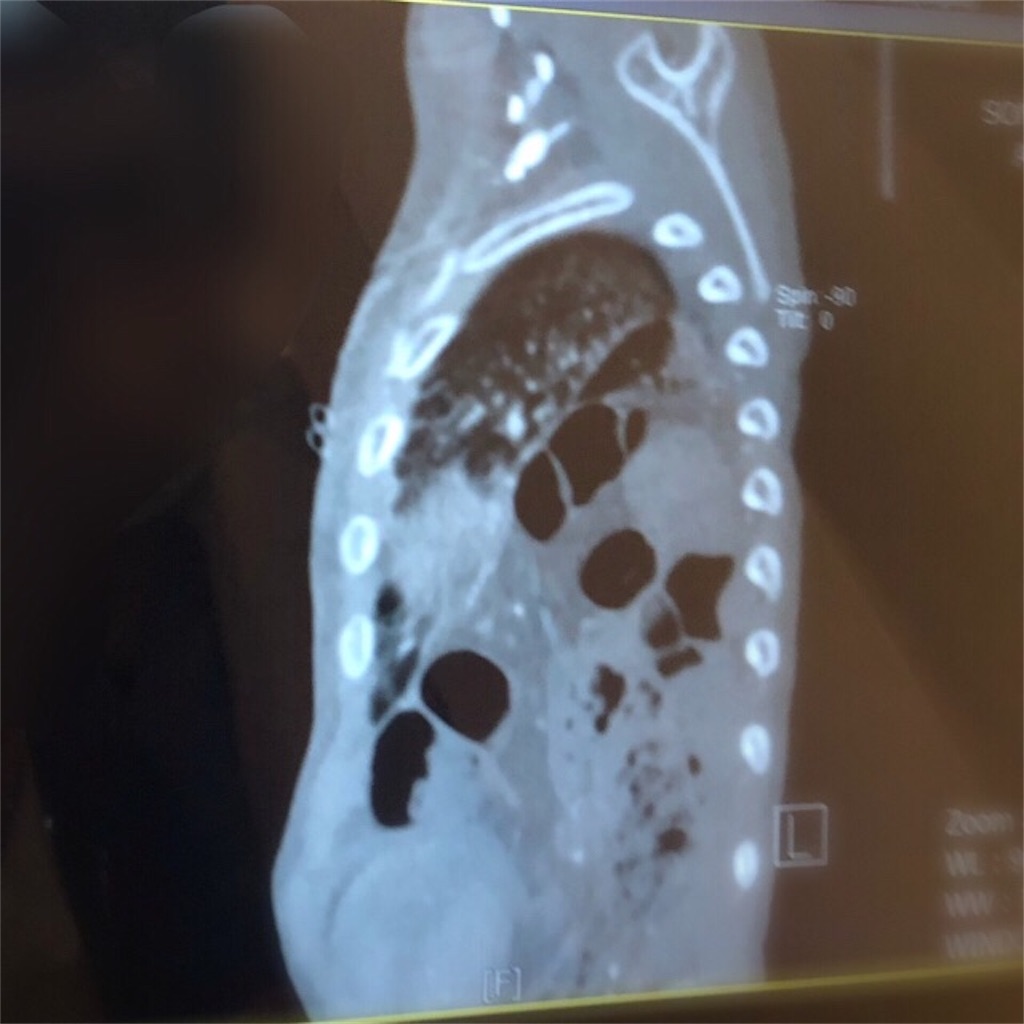

やはり、横隔膜に相当大きな穴があることがわかった。

横隔膜に開いた穴はかなり大きく、すぐに腸が締め付けられたりする可能性は低いそうだ。

こんなに肺が押されているんじゃ苦しいだろうし、便秘がちなのも納得だ。